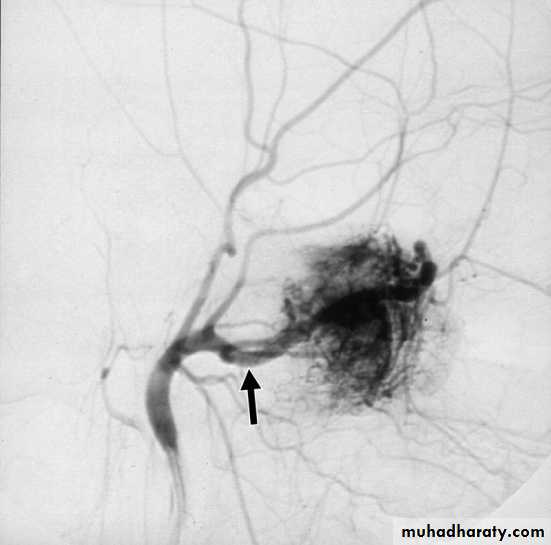

c. External carotid arteriography.

1. Surgical excision Haemorrhage is the main danger of operation, so adequate blood should be prepared before the operation.2. Embolization is indicated preoperatively to control the vascularity of the tumor.